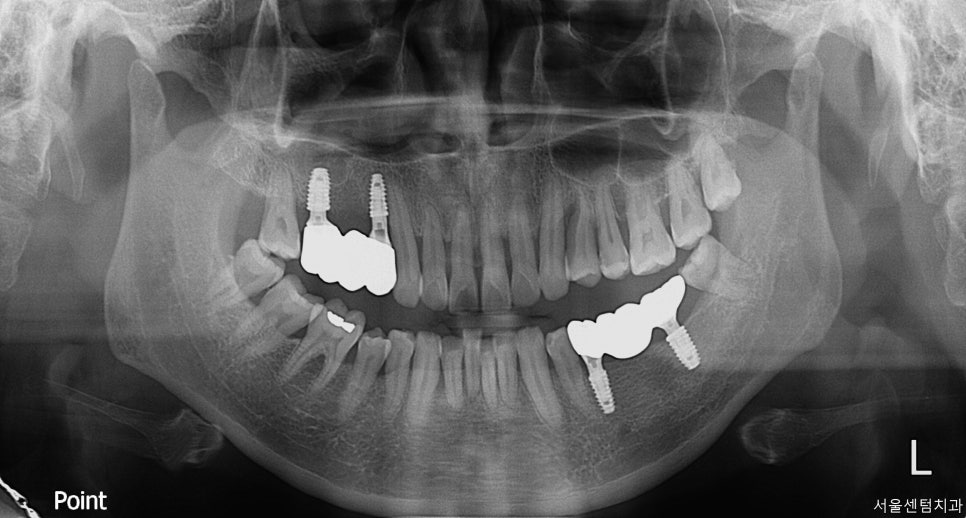

40대의 여성 환자분

첫 내원은 더위가 가시고

가을이 찾아오기 시작할 즈음이었죠.

처음 오셨을 때 이미 어금니가

여러개 없는 상황이었습니다.

일단 파노라마 찍고 치근단 엑스레이

CT까지 확실히 촬영한 후 확인했습니다.

자세히 살펴보면 치석도 치아 사이사이

치간 사이에 꽤나 많은 케이스입니다.

그렇다 보니 당연히 잇몸의 건강 또한

좋은 상황은 아니었고요.

전반적으로 치아관리가 잘 되고 있는

케이스로 보기는 어렵습니다.

먼저 하악의 임플란트 먼저 식립을 진행하였는데요.

처음 방문하신 이후 약 10일 후에 진행하였습니다.

그 이후 상악은 한 달 뒤쯤 식립하였습니다.